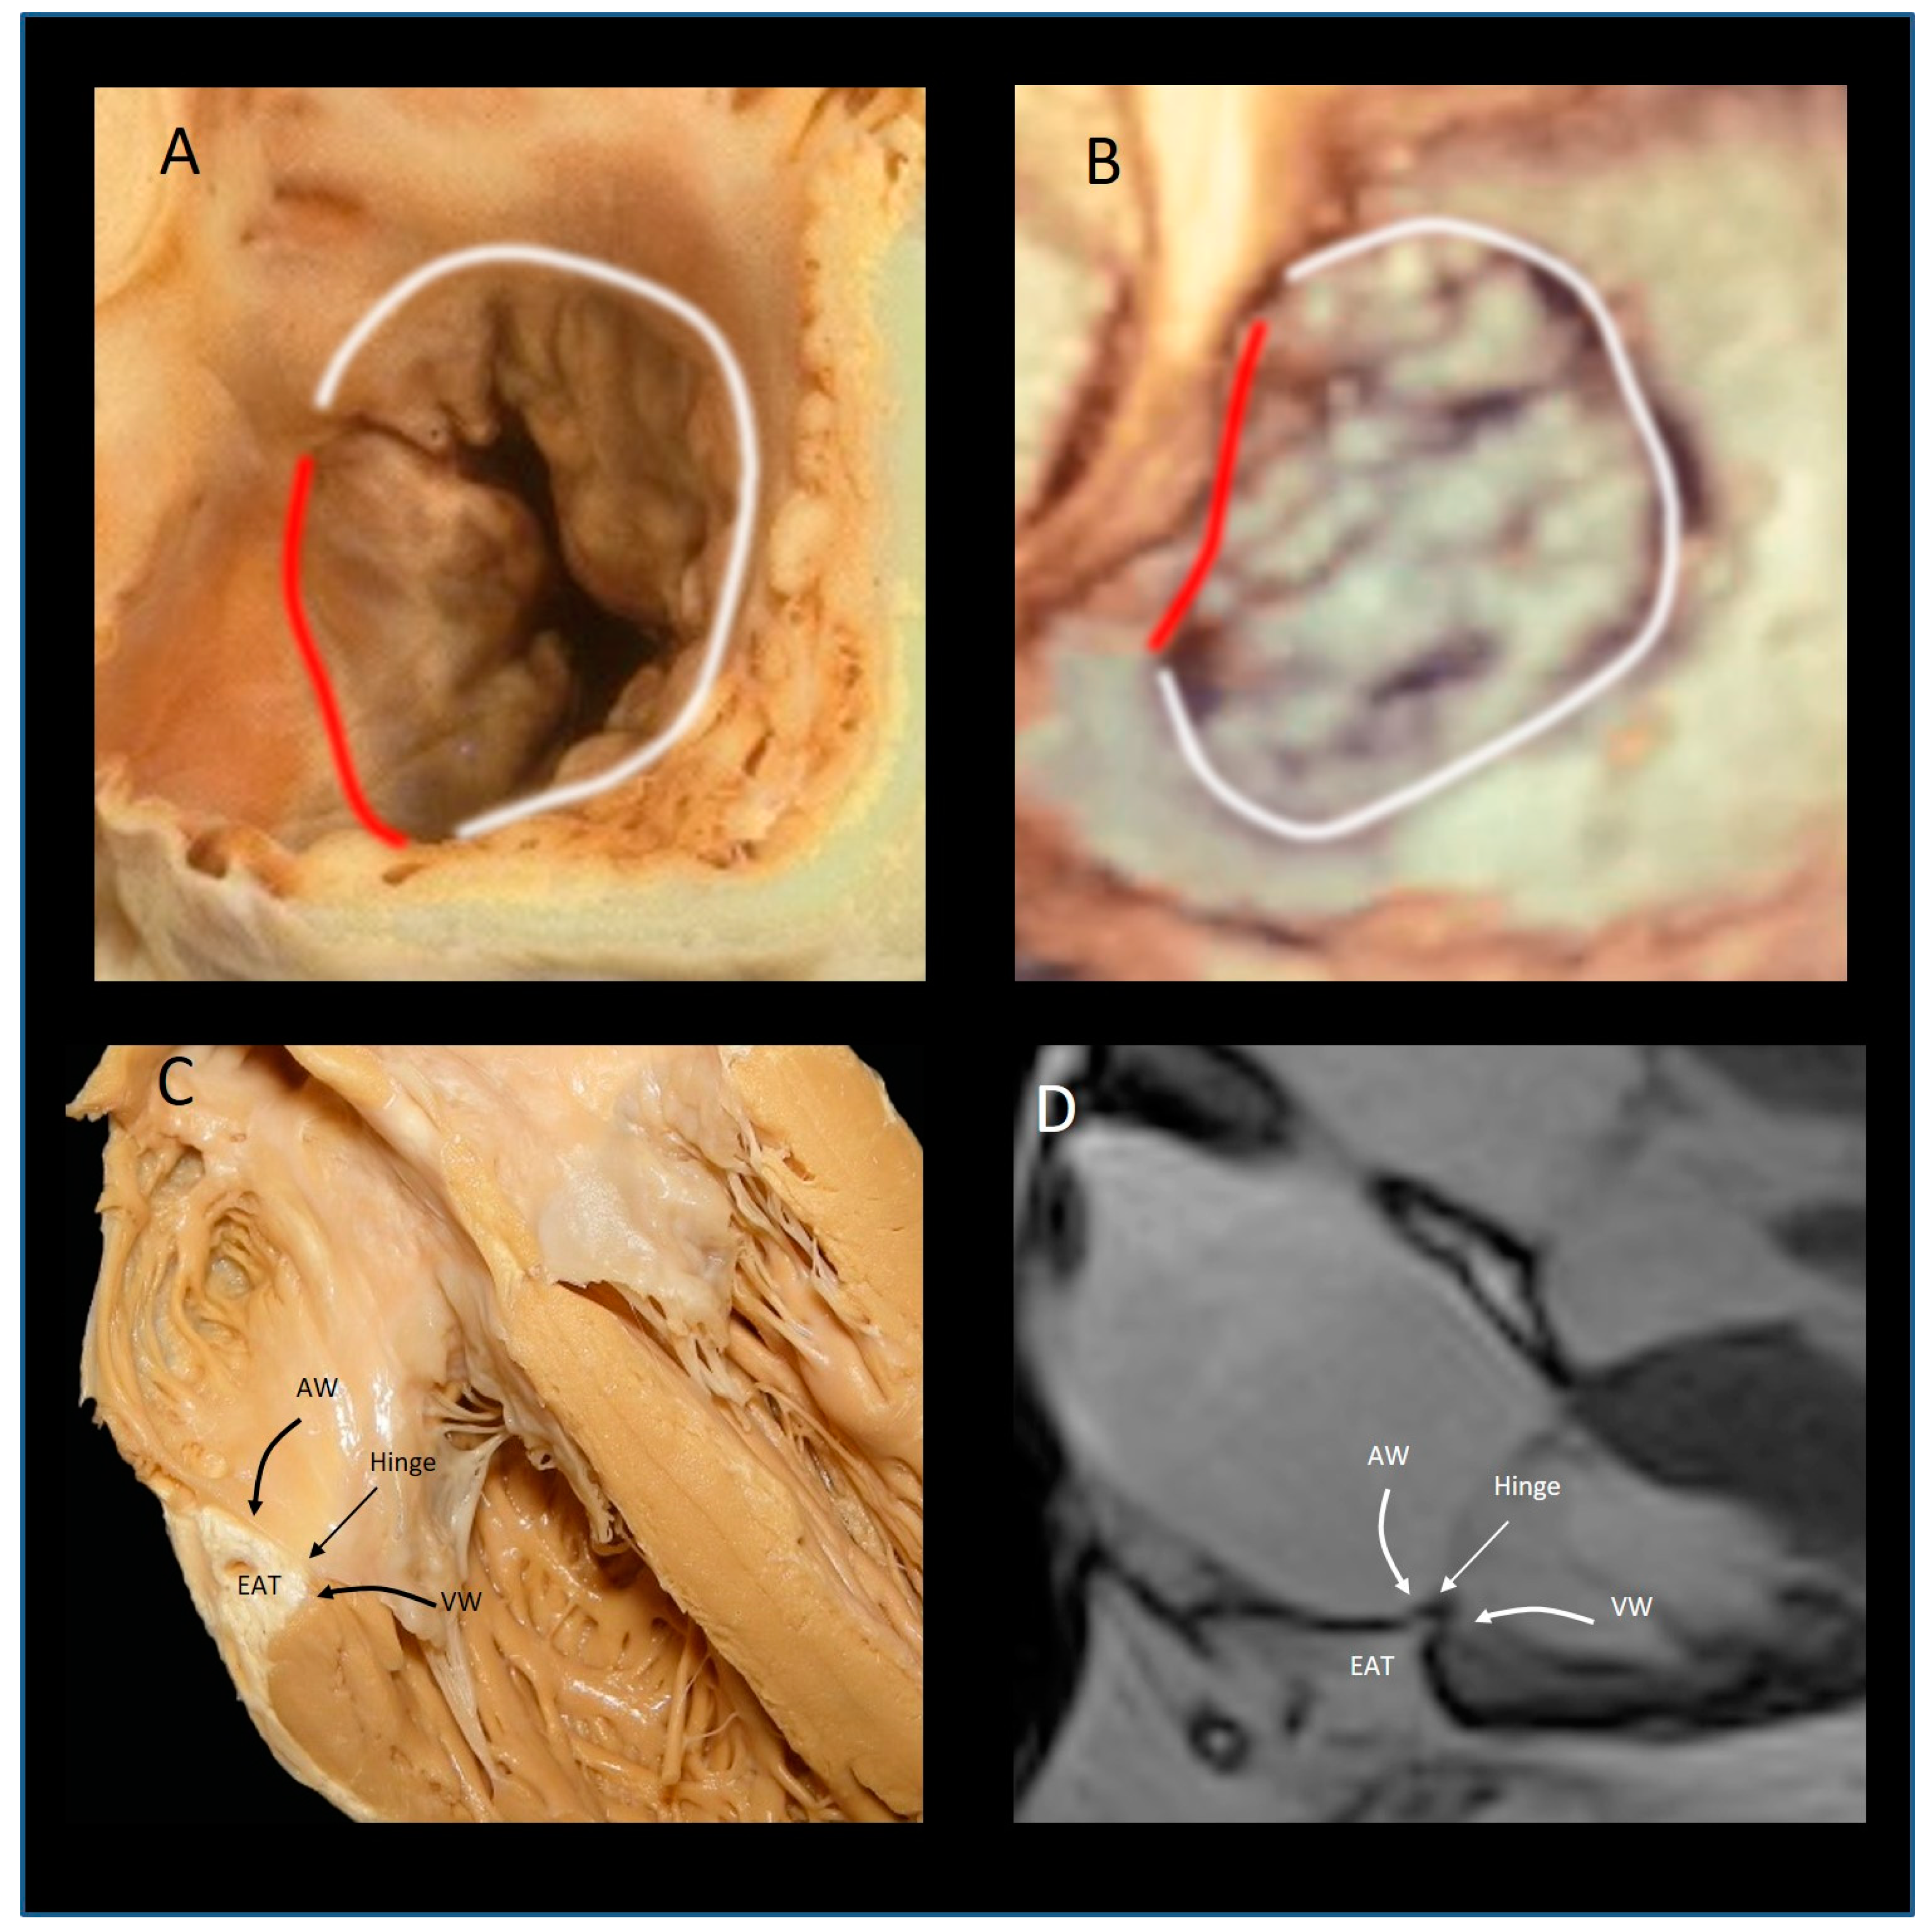

The “Mural” Annulus

4. The “Septal” Annulus